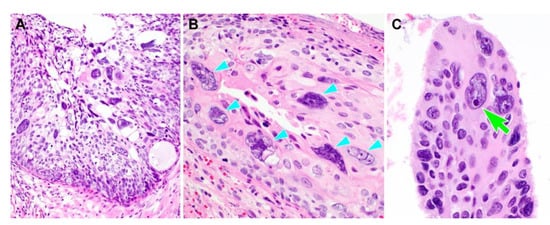

Representative photomicrographs showing histological features of PHSILs are shown in Figure 1. The diameter of PHSIL nuclei was at least four times larger than that of normal basal cells. Enlarged endocervical glands due to PHSIL involvement were readily identifiable at scanning magnification. Markedly increased mitotic activity and frequent atypical mitotic figures were observed. There were obvious nuclear pleomorphism and hyperchromasia as well as large, conspicuous nucleoli and frequent multinucleation (Figure 2). PHSILs involved both the surface epithelium and endocervical glands in 24 (77.4%) cases and the surface epithelium alone in seven (22.6%) cases. All PHSIL cases with endocervical glandular extension showed expansive growth. In all but two cases involving the glands, PHSILs involved multiple endocervical glands (Figure 3). The presence of variable-sized endocervical lumina at the periphery of the involved glands indicated their intraepithelial nature. Intraluminal necrotic and parakeratotic cellular debris with admixed mucin was frequently observed.

Figure 1. Histological features of pleomorphic high-grade squamous intraepithelial lesion (PHSIL). (A) Compared to conventional HSIL (two light green arrows), PHSIL (middle lower) displays significant nuclear enlargement and hyperchromasia that is easily identifiable at low-power magnification. (B) PHSIL exhibits expansile involvement of the endocervical gland. The presence of residual endocervical glandular epithelium along the luminal surface (four light blue arrowheads) indicates the intraepithelial nature. (C) An abnormal mitotic figure is detected (yellow circle). Hematoxylin and eosin staining. Original magnification: (A) = 100×, (B) = 200×, (C) = 400×.